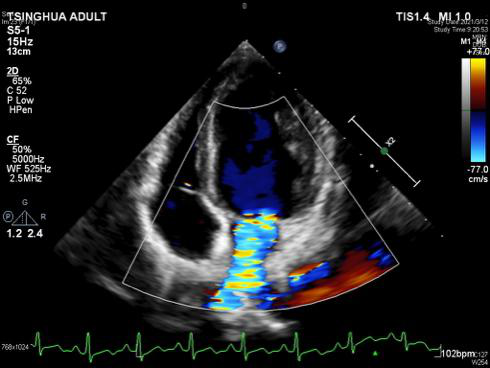

图一 心脏超声显示二尖瓣大量反流 图二 左侧腘动脉以下闭塞

与预期一样,二尖瓣由于细菌的长时间侵蚀,薄薄的后叶瓣叶已经穿孔,前叶瓣缘也存在赘生物。为了保住二尖瓣,崔晓征用小圆刀在薄薄的瓣膜上进行了显微操作,沿着二尖瓣的前叶轻轻地拨除附着在上面的赘生物,深一点就会损伤瓣膜,浅一点就会造成赘生物清楚不彻底,最终成功剥离了前叶的赘生物,同时没有损伤二尖瓣前叶。因为洋洋二尖瓣后叶穿孔,切除穿孔部分的二尖瓣,崔晓征对后叶进行了环缩,心脏复跳后,超声显示仍存在少中量的反流。

通常这种情况下想保住二尖瓣很难,本可以按照计划将二尖瓣换成机械瓣,但考虑以后孩子要长期服药,还有面临二次手术风险的可能。“我们还是尽量让他使用自己的瓣膜,不要给孩子留下遗憾!”这样的信念使得崔晓征毫不犹豫地再次打开洋洋的心脏,对二尖瓣进行了二次修复。心脏再次复跳后,超声显示瓣膜干干净净,反流几乎完全消失,洋洋的二尖瓣保住了!。